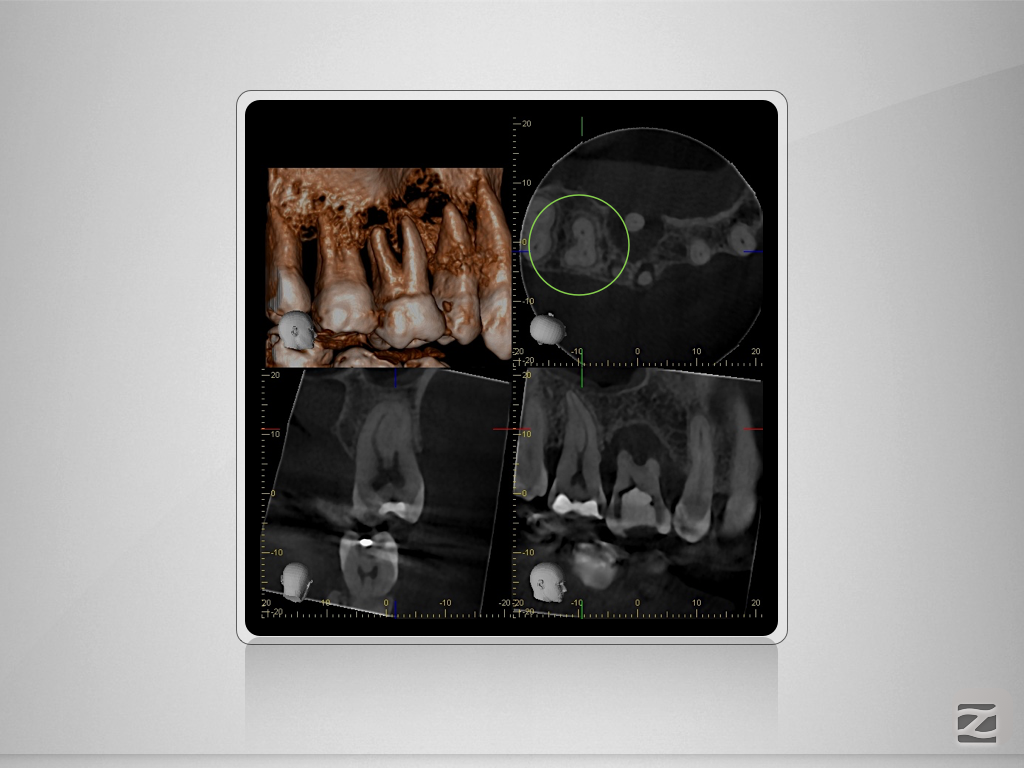

17D.008

Gewusst, wo’s lang geht.